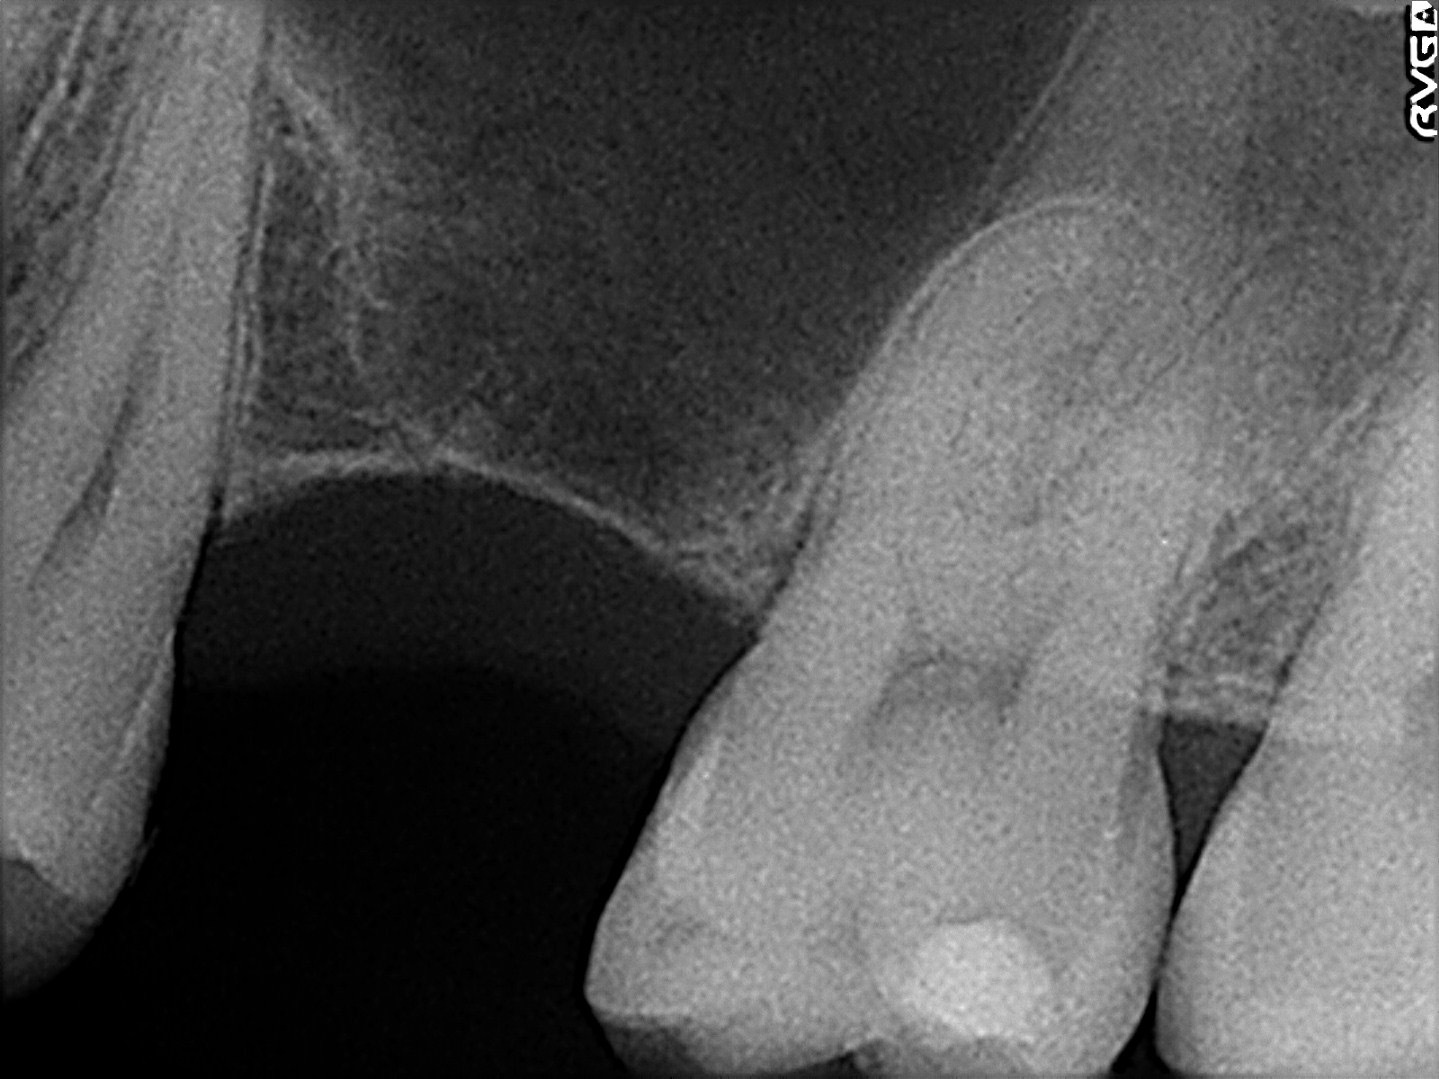

駒込駅から徒歩3分と利便性の高い場所に医院を構える芥川歯科は「患者さんと向き合い、生涯の健康を支える本質的な治療を提供する」をモットーに地域密着型の医療を提供する歯科医院です。インプラント治療をはじめ、入れ歯・ブリッジといった補綴全般に対応する総合力を持っており、歯科医師としての意見を押し付けることなく、患者さんとの丁寧な対話を通じて共に「希望に沿った治療」を目指す姿勢が、幅広い世代の患者さんからの信頼を集めています。インプラントは、数ある歯科治療の分野の中でも特に繊細な対応が求められる分野だからこそ治療環境の充実化にもこだわられており、歯科用CTやマイクロスコープ、手術用のガイドシステムなどの先進的な機器を積極的に導入することで、治療の質の向上に努められている点は大きな安心材料となるのではないでしょうか。また、歯科治療に対する不安やネガティブなイメージにも配慮した治療を実践しているそうで、切開を伴わないフラップレス手術を行い、出来る限り低侵襲で体への負担を考慮してオペを行うなど、ペインコントロールや術後の配慮が行き届いているため、歯科治療への恐怖心が強い方も健康への一歩を踏み出すことができるでしょう。